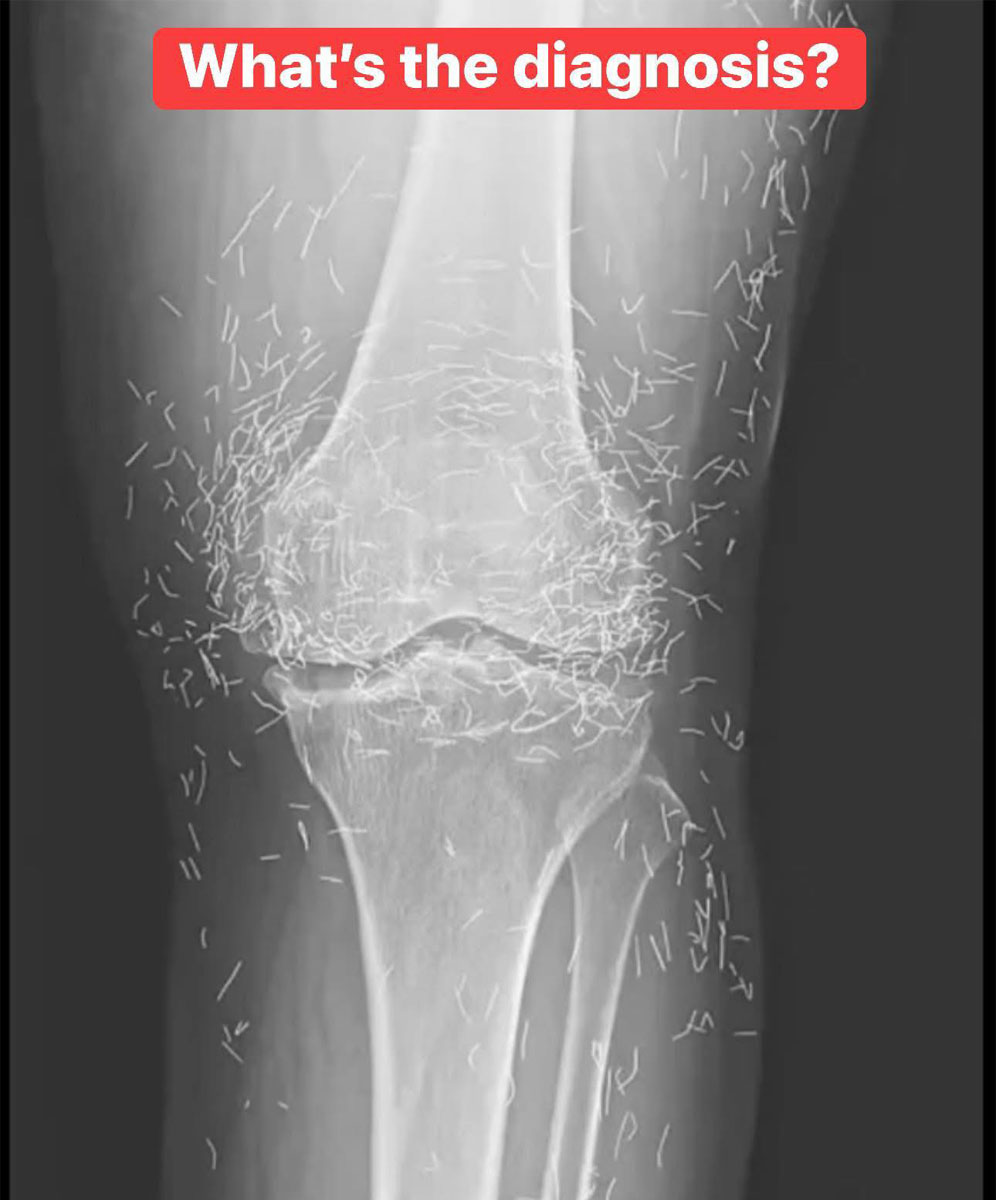

X-Ray Reveals Hundreds of Gold Needles in Woman’s Knees

Upon reviewing an X-ray of an elderly woman’s painful knees, doctors made a startling discovery: her tissue contained hundreds of tiny, retained gold acupuncture needles. The 65-year-old patient from South Korea suffered from osteoarthritis and had sought acupuncture after conventional pain medication proved ineffective and caused stomach issues.

Acupuncture is an alternative medical practice that involves inserting needles at specific points on the body to relieve pain or treat various conditions. In this particular treatment, gold needles were intentionally left embedded in her tissue to provide ongoing stimulation.

Retained needles can also complicate medical imaging. They may obscure anatomical details on an X-ray, making accurate diagnosis more challenging.